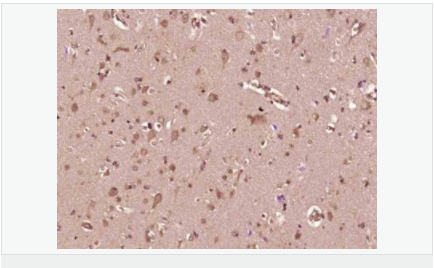

| 產品應用 | WB=1:500-2000 ELISA=1:5000-10000 IHC-P=1:100-500 IHC-F=1:100-500 Flow-Cyt=0.2μg/Test ICC=1:100-500 IF=1:100-500 (石蠟切片需做抗原修復) not yet tested in other applications. optimal dilutions/concentrations should be determined by the end user. |

| 產品介紹 | Platelet-derived growth factor is a potent mitogen for cells of mesenchymal origin. Binding of this growth factor to its affinity receptor elicits a variety of cellular responses. It is released by platelets upon wounding and plays an important role in stimulating adjacent cells to grow and thereby heal the wound. Antiparallel disulfide-linked dimer of nonidentical (A and B) chains. Homodimers of A and B chains are implicated in transformation processes. The long form contains a basic insert which acts as a cell retention signal. A-A and B-B, as well as A-B, dimers can bind to the PDGF receptor. It belongs to the PDGF/VEGF growth factor family. Function: Growth factor that plays an essential role in the regulation of embryonic development, cell proliferation, cell migration, survival and chemotaxis. Potent mitogen for cells of mesenchymal origin. Required for normal lung alveolar septum formation during embryogenesis, normal development of the gastrointestinal tract, normal development of Leydig cells and spermatogenesis. Required for normal oligodendrocyte development and normal myelination in the spinal cord and cerebellum. Plays an important role in wound healing. Signaling is modulated by the formation of heterodimers with PDGFB. Subunit: Homodimer; antiparallel disulfide-linked dimer. Heterodimer with PDGFB; antiparallel disulfide-linked dimer. The PDGFA homodimer interacts with PDGFRA homodimers, and with heterodimers formed by PDGFRA and PDGFRB. The heterodimer composed of PDGFA and PDGFB interacts with PDGFRA homodimers, and with heterodimers formed by PDGFRA and PDGFRB. Interacts with CSPG4. Subcellular Location: Secreted. Note=Released by platelets upon wounding. Tissue Specificity: Platelet-derived growth factor is a potent mitogen for cells of mesenchymal origin. Binding of this growth factor to its receptor elicits a variety of cellular responses. It is released by platelets upon wounding and plays an important role in stimulating adjacent cells to grow and thereby heals the wound. Similarity: Belongs to the PDGF/VEGF growth factor family. SWISS: P01127 Gene ID: 5154 Database links: Entrez Gene: 5154 Human Entrez Gene: 5155 Human Entrez Gene: 18590 Mouse Entrez Gene: 18591 Mouse Omim: 173430 Human Omim: 190040 Human SwissProt: P01127 Human SwissProt: P04085 Human SwissProt: P20033 Mouse SwissProt: P31240 Mouse Important Note: This product as supplied is intended for research use only, not for use in human, therapeutic or diagnostic applications. PDGF-A(platelet-dirived growth factor-A)是一種堿性蛋白,pdgf促進細胞分裂、增值同時,可誘導c-fos、c-myc等蛋白表達增強。 主要作用:參與組織和血管修復、促進平滑肌細胞、成纖維細胞迅速增值。分子量為28-35kDa,分為兩個亞基(A、B鏈)通過二硫鍵結合而成的兩條多肽鏈的異二聚體。最新研究發現了PDGF家族兩種新的基因PDGF-C、PDGF-D。 |